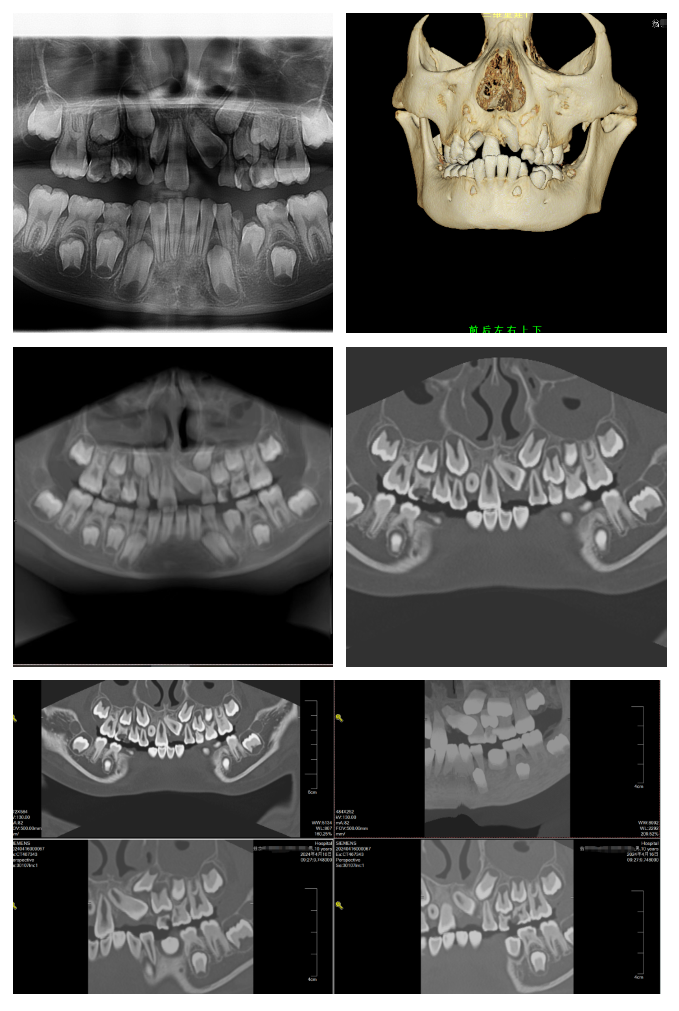

一位10岁的患者来到我院口腔科就诊,患者妈妈说患者近一年发现上颌前牙萌出后牙列不齐,听闻我院有上海帮扶专家在,特意带孩子前来就诊。完善相关检查后,诊断为:上颌骨发育不足、前牙反颌、21阻生埋伏牙、12畸形牙异位萌出,需要外科手术联合固定矫治器+活动颌垫矫治器。

患者三维成像

上海援滇专家段阿竹据介绍:口腔内在发育过程中,由于收到不同的生长阻力,影响到上颌前牙的萌出,临床上,上颌前牙埋伏阻生导致错颌畸形较为常见。对患者的牙弓形态、咬合力以及面型发育均造成影响。可以通过外科手段对上颌埋伏阻生牙进行定位牵引治疗,通过多种矫治器联合应用,改善牙齿拥挤、错位等情况,整体提升牙齿功能和面部美观。而口腔CT三维重建成像可以从三维角度对组织情况进行反映,发现口腔X光片的投照角度不能发现的、或者更细微的病变;它的三维重建效果能够对骨组织情况、下颌关节情况进行准确评价,协助医生进行手术前方案设计,以及术后科学评价。